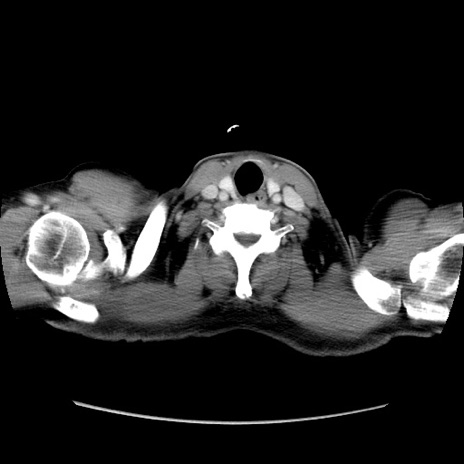

冠状断像

【症例】60歳代 男性

【主訴】右鼠径部膨隆

【現病歴】1年程前より右鼠径部膨隆あり。自己にて還納可能だったため放置していた。3時間前より右鼠径部の脱出を認め、還納困難となり受診。

【既往歴】高血圧

【身体所見】右鼠径部に小児頭大の膨隆あり。弾性硬であり、用手還納は困難。左鼠径部にも膨隆を認める。脱出はなし。

【データ】WBC 15500、CRP 測定なし